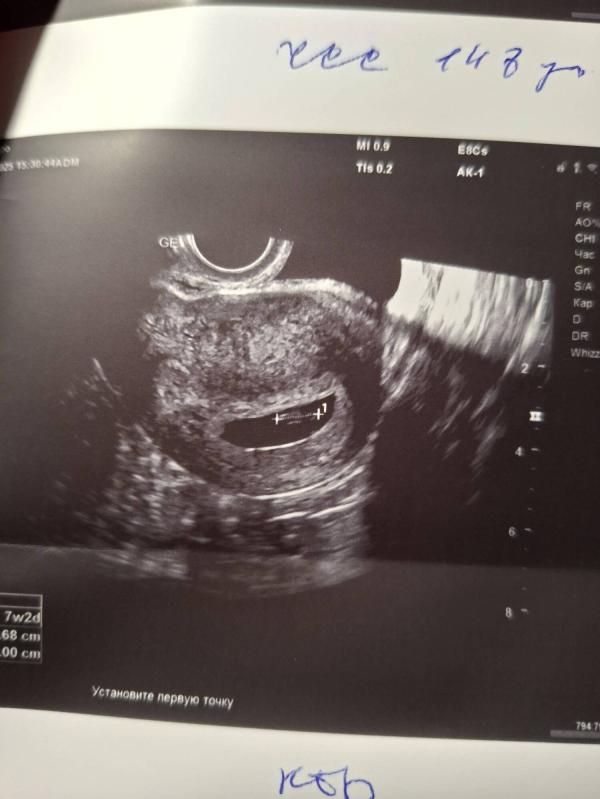

Продолжает расти наша бусинка.

Если смотреть по расположению плода и частоте сердечных сокращений, то скорее всего у нас растёт девочка 😃 позже мы узнаем насколько это правдивая информация)

Типа у девочки чсс меньше? Мне пока предположили девочку, чсс 150 было. Но я не верю. На 16 неделе схожу для подтверждения

Наоборот, у девочки чсс выше 140, а у мальчиков ниже этого значения.

Нам показатель выше 140, то говорят, что девочка. Но естественно, что научных доказательств этого метода нет. Это скорее развлечься и погадать)